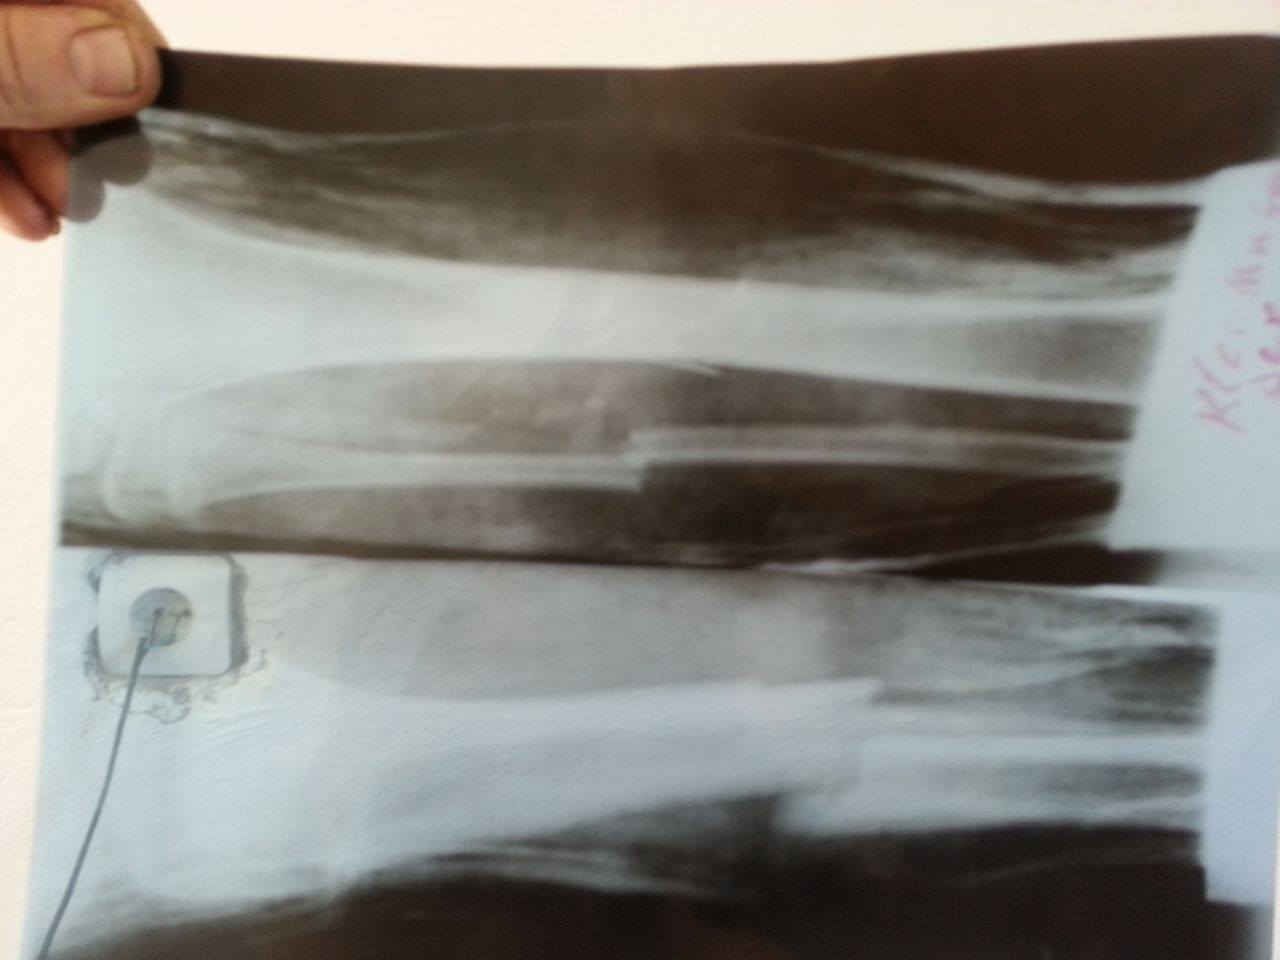

Babai i mjeruar ka bërë apel që dikush të ofrohet për ndihmë, në mënyrë që 13-vjeçari Kleo Muça, të bëhet operacion në këmbë. Këmba e djathtë ka pësuar fraktura të rënda, duke u thyer e gjitha, ndërsa këmba e majtë ka marrë vetëm krisje. Atë ditë, Kleo ka qenë duke shkuar në shkollë se bashku me shokët e tij. Këta të fundit lajmërojnë familjen, të cilët nxitojnë për ta dërguar djalin drejt Spitalit Kirurgjik të Elbasanit, për t’i dhënë ndihmën e parë.

Pas grafisë, mjekët konstatojnë se gjendja e këmbëve të djalit është serioze, frakturat janë të rënda dhe vetëm ndërhyrja kirurgjikale mund të ndihmojë rikuperimin e vogëlushit. Prindërit thonë se operacioni sipas mjekëve kushton 5 mijë euro, shumë e cila është e papërballueshme për familjen Muça nga Kodër Bujarasi, që të vetmet të ardhura për jetesë ka ndihmën sociale prej 7 mijë lekësh të reja dhe të ardhurat që siguron nga shitja e barishteve të ndryshme.